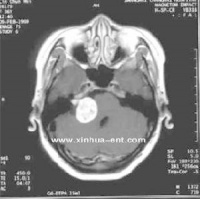

(2)CT及MRI扫描:CT表现为瘤体呈等密度或低密度,少数呈高密度影像。肿瘤多为圆形或不规则形,位于内听道口区,增强效应明显。MRIT1加权像上呈略低或等信号,在T2加权像上呈高信号。第四脑室受压变形,脑干及小脑亦变形移位。注射造影剂后瘤实质部分明显均一强化,囊变区不强化。

(3)CT及MRI检查:目前听神经鞘瘤诊断的标准是Gd-DTDA增强的MRI,特别是当肿瘤很小(<1cm)或在内听道内,CT扫描阴性又高度怀疑肿瘤存在时应该进行GD-DTPA增强的MRI。CT与MRI两种检查有相辅相成的作用,如CT发现有病侧内听道扩大时,增强CT可发现肿瘤对于估计中颅窝入路时颞骨的气化程度及高颈静脉球与后半规管及底的距离有帮助。如果病人已作了CT而肿瘤较大,MRI可提供对脑干压迫的范围Ⅳ脑室是否通畅脑积水、是否存在的情况对可疑听神经鞘瘤或CT检查难于确定时,全序列的MRI可做出鉴别诊断。但也要注意Gd-DTPA的可能假阳性,这与内听道内神经的炎症或蛛网膜炎有关;任何小的接近底部的增强病变应该在六月后作MRI复查,以评估其生长情况。